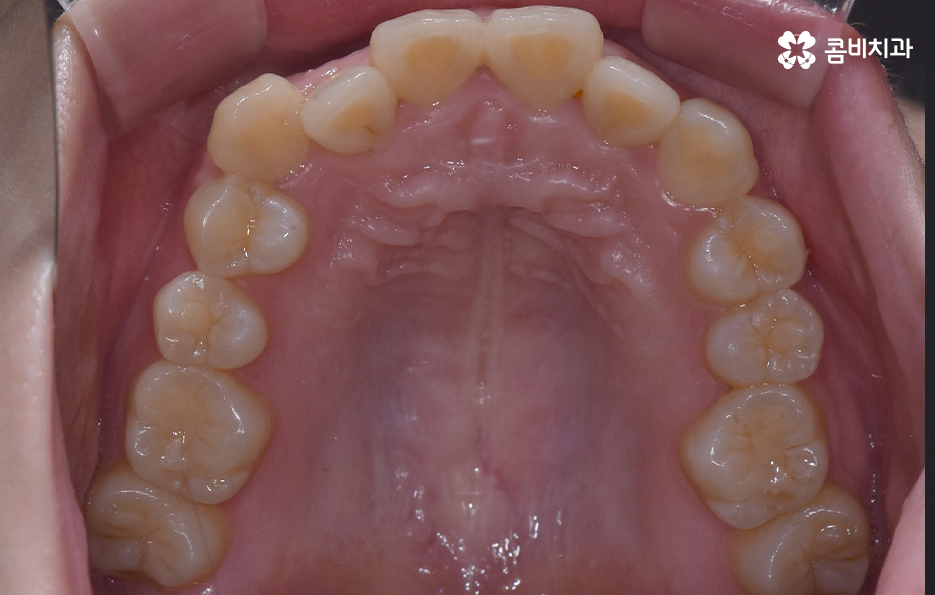

오늘 덧니 비발치 교정 사례로 보시는 환자분의 경우에는 윗니와 아랫니 앞니 부분에 조금씩 덧니가 있는 상태로 덧니를 제외하면 대체적으로 치열 상태는 고른 편이며 덧니 교정 사례 중에서는 돌출입도 함께 개선해야 하는 경우가 많지만 위 환자분의 경우에는 돌출입의 정도가 양호했고 입술라인 역시도 정상 범위에 가까웠기 때문에 발치를 필요로 하지 않았지만 치아의 이동 공간과 보다 자연스러운 입술라인 그리고 얼굴형과의 조화를 고려하여 악궁 확장과 어금니 후방 이동을 적절히 활용하여 교정 치료가 진행되었다고 볼 수 있어요